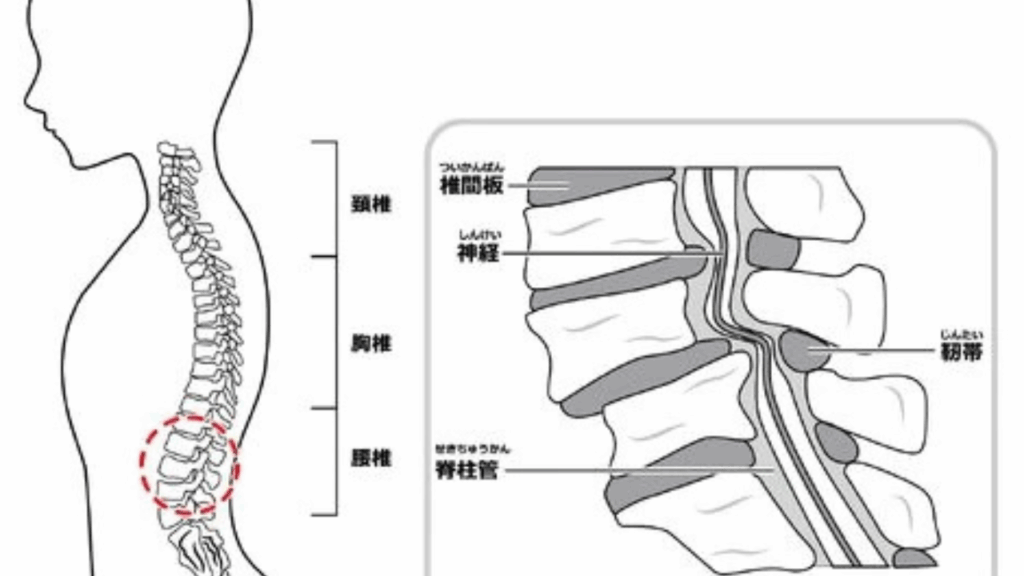

背骨の後ろ側に神経が通っています。その神経の通り道を「脊柱管」と言います。

腰に負担がかかって、腰の骨に棘が出たり、腰と腰の間の「椎間板」潰れたり、骨事態が潰れたりして

脊柱管が狭くなる腰の病気です。

腰に負担がかかって神経が通っている脊柱管が狭く(狭窄)なって尻や太もも、足にしびれや痛みが出てしまいます。